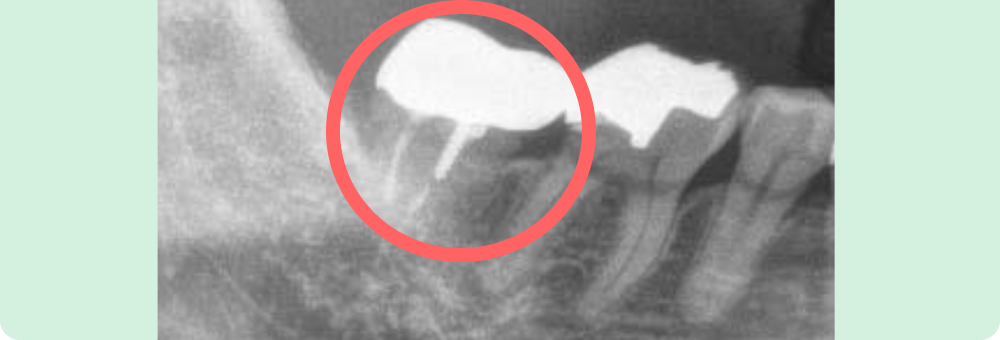

左下奥歯の再植

根っこの治療を開始しましたがあまりよくならず、本来なら抜歯ケースですが、患者さんと相談し一度、再植をすることになりました。

いったん抜歯し、その場で薬を塗布し再度、戻しました。

現在でも痛み無く十分機能しています。

主訴

左下奥歯が腫れて痛い

患者様

50代/女性

治療期間

4ヶ月

費用

約20,000円(税込)保険内